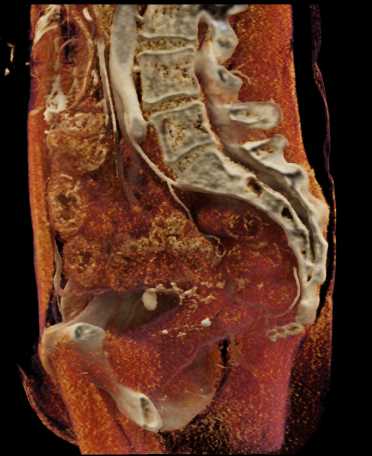

Urachal Carcinoma of the Bladder